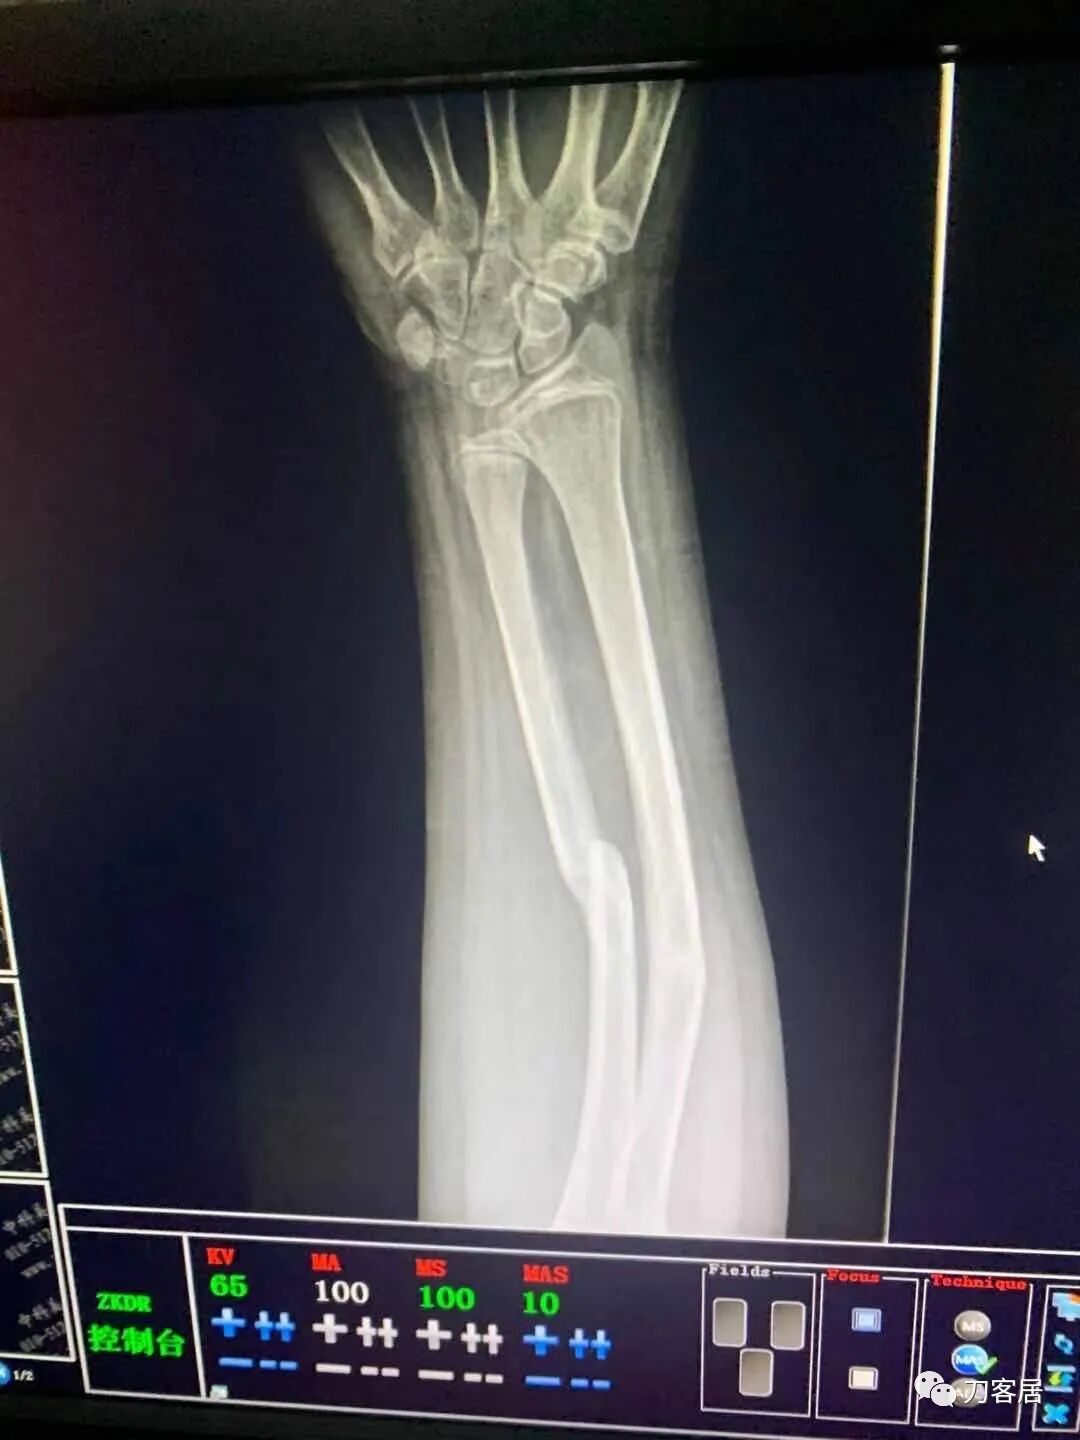

下面是这个6岁孩子,尺桡骨远端双骨折的术前及术后片子和外观照片。

1.  这是一个很简单的6岁儿童无移位的尺桡骨远端骨折。没有皮肤损伤,没有移位,没有骨折碎块儿。

2.  这个骨折处理起来也很简单,单纯的打石膏托或者中医的小夹板,或者正规的包括腕关节和肘关节的管型石膏外固定4周即可治愈该骨折。实在不行,如果这个孩子比较听话,不太调皮的话,用一本书,一个三角巾悬吊固定4周,都可以治愈该骨折。但是给这个患者用外固定架做了手术,而且桡骨远端的几颗克氏针距离骨折线太近,其中一枚克氏针进入到骨折间隙内。从这个术中图片来看,术者的外固定手术技术也有待于进一步的提高。毕竟术者应该还很年轻。从X线片来看,前臂及手的尺侧有不透光影,应该还使用了外固定石膏绷带托,而且我猜测应该是高分子的石膏绷带托,这个是纯属猜测,不一定是对的,不过如何解释前臂尺侧的不透光影呢?如果真是用了石膏绷带外固定的话,那为啥要做手术呢?外固定架术后就不该再用石膏绷带托辅助了。

这个病例,6岁的孩子,尺桡骨骨折在同一个平面,且都为小斜行骨折,不是螺旋形,不是粉碎性,不是成角移位性,属于稳定性尺桡骨双骨折,根本就没有任何手术的适应症。